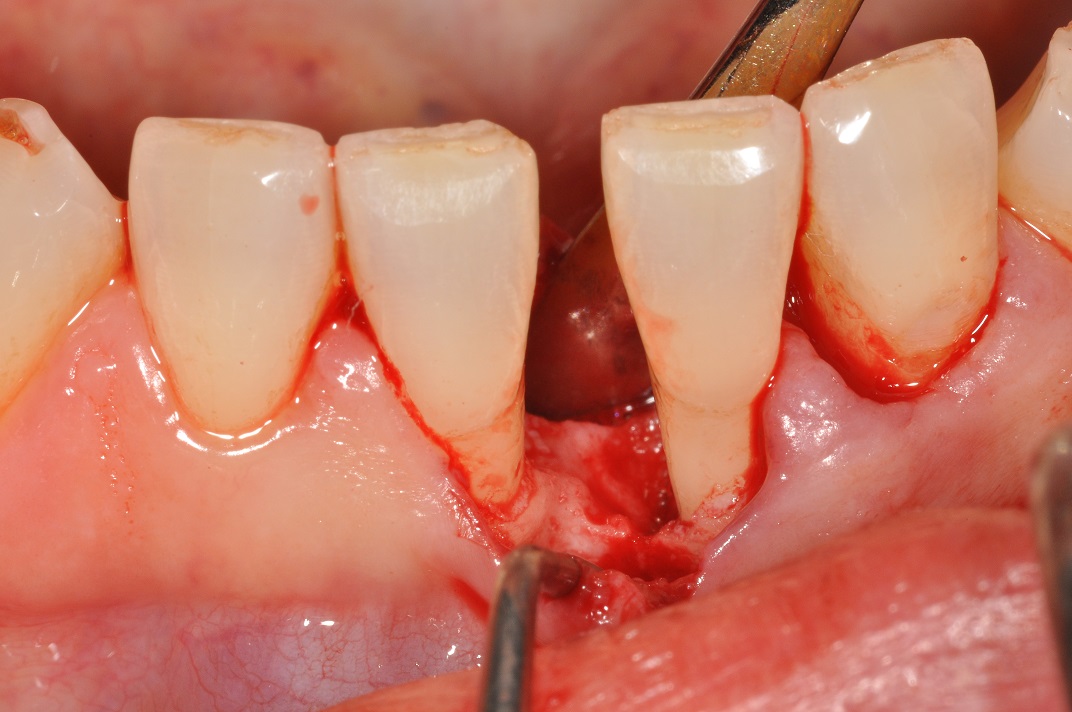

-

04/13 - Soft tissue augmentation using an autogenous connective tissue graft.